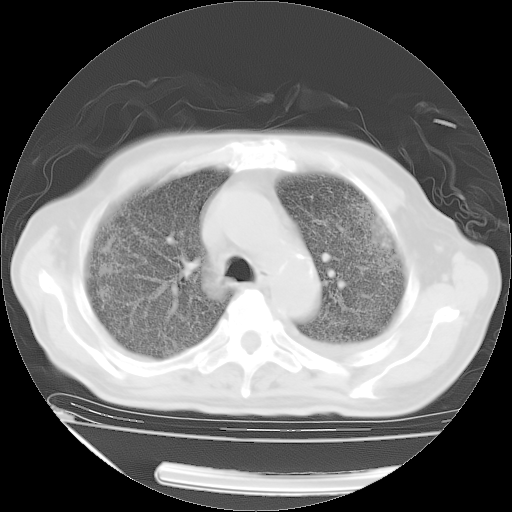

甲强龙80mg/日+抗结核治疗(异烟肼+利福霉素+乙胺丁醇)10天。复查肺部CT。

治疗10天肺部CT